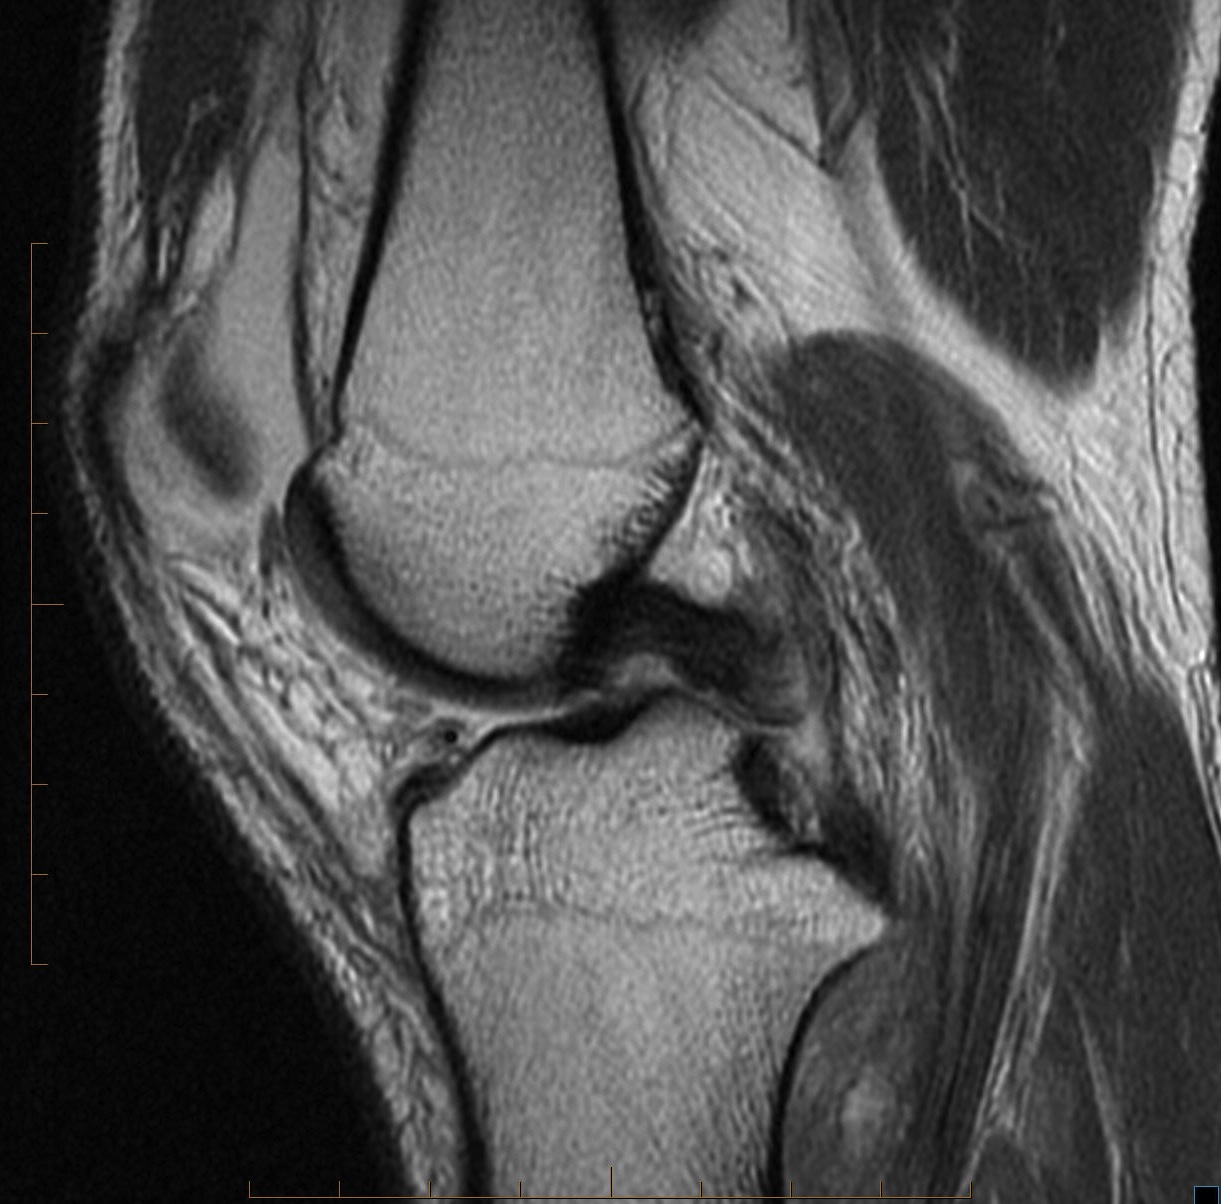

Figure 1 for case PCL tear

Figure 1

PCL tear